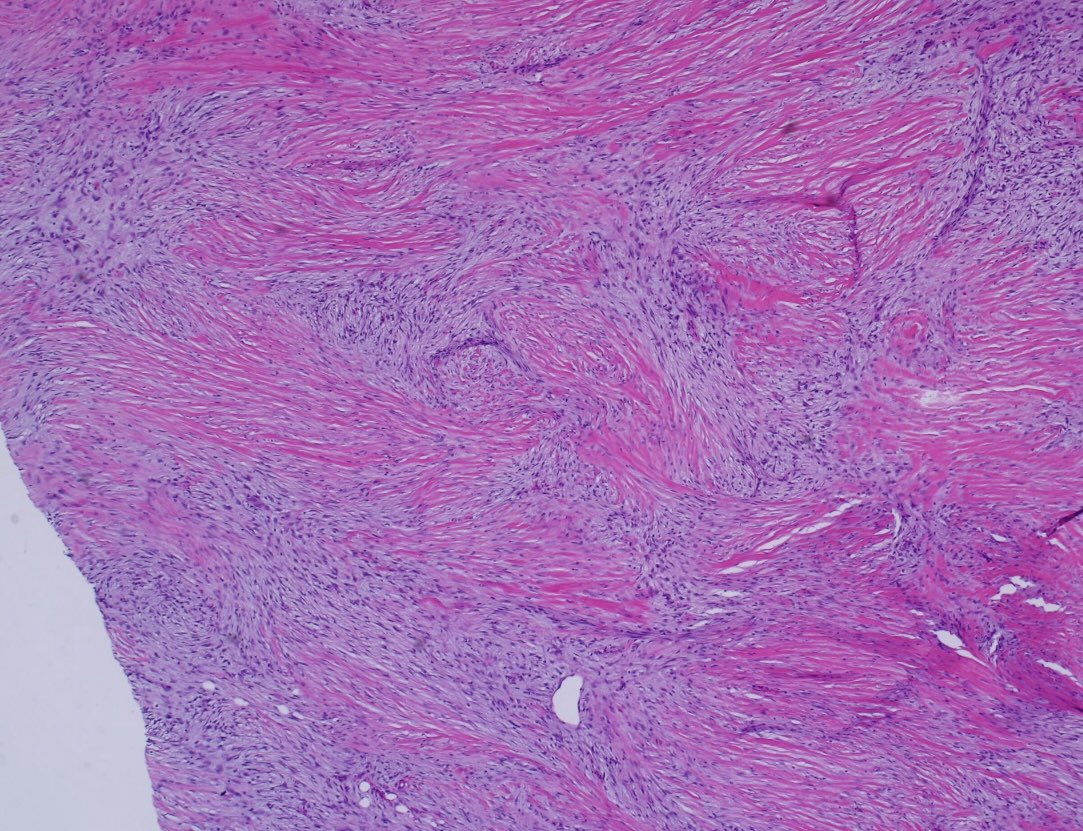

Clinicopathologic, immunohistochemical and genomic characterization of urothelial carcinoma with myxoid and chordoid features